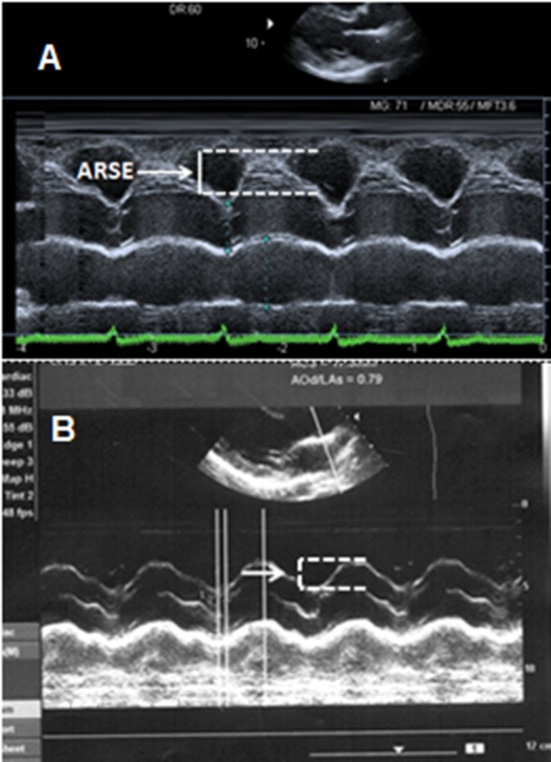

Aortic root systolic excursion (ARSE) was assessed by placing M-mode cursor on center of the root of aorta (Figure 1). The amplitude of systolic movement of anterior aortic wall was calculated to represent ARSE (mm). The average of 3 measures were obtained from the far wall in the long parasternal axis view.15

Figure 1 A- Aortic root systolic excursion (ARSE) in patients with good exercise tolerance (6MWTD≥300m). B- ARSE in patients with reduced exercise tolerance (6MWTD<300 m).